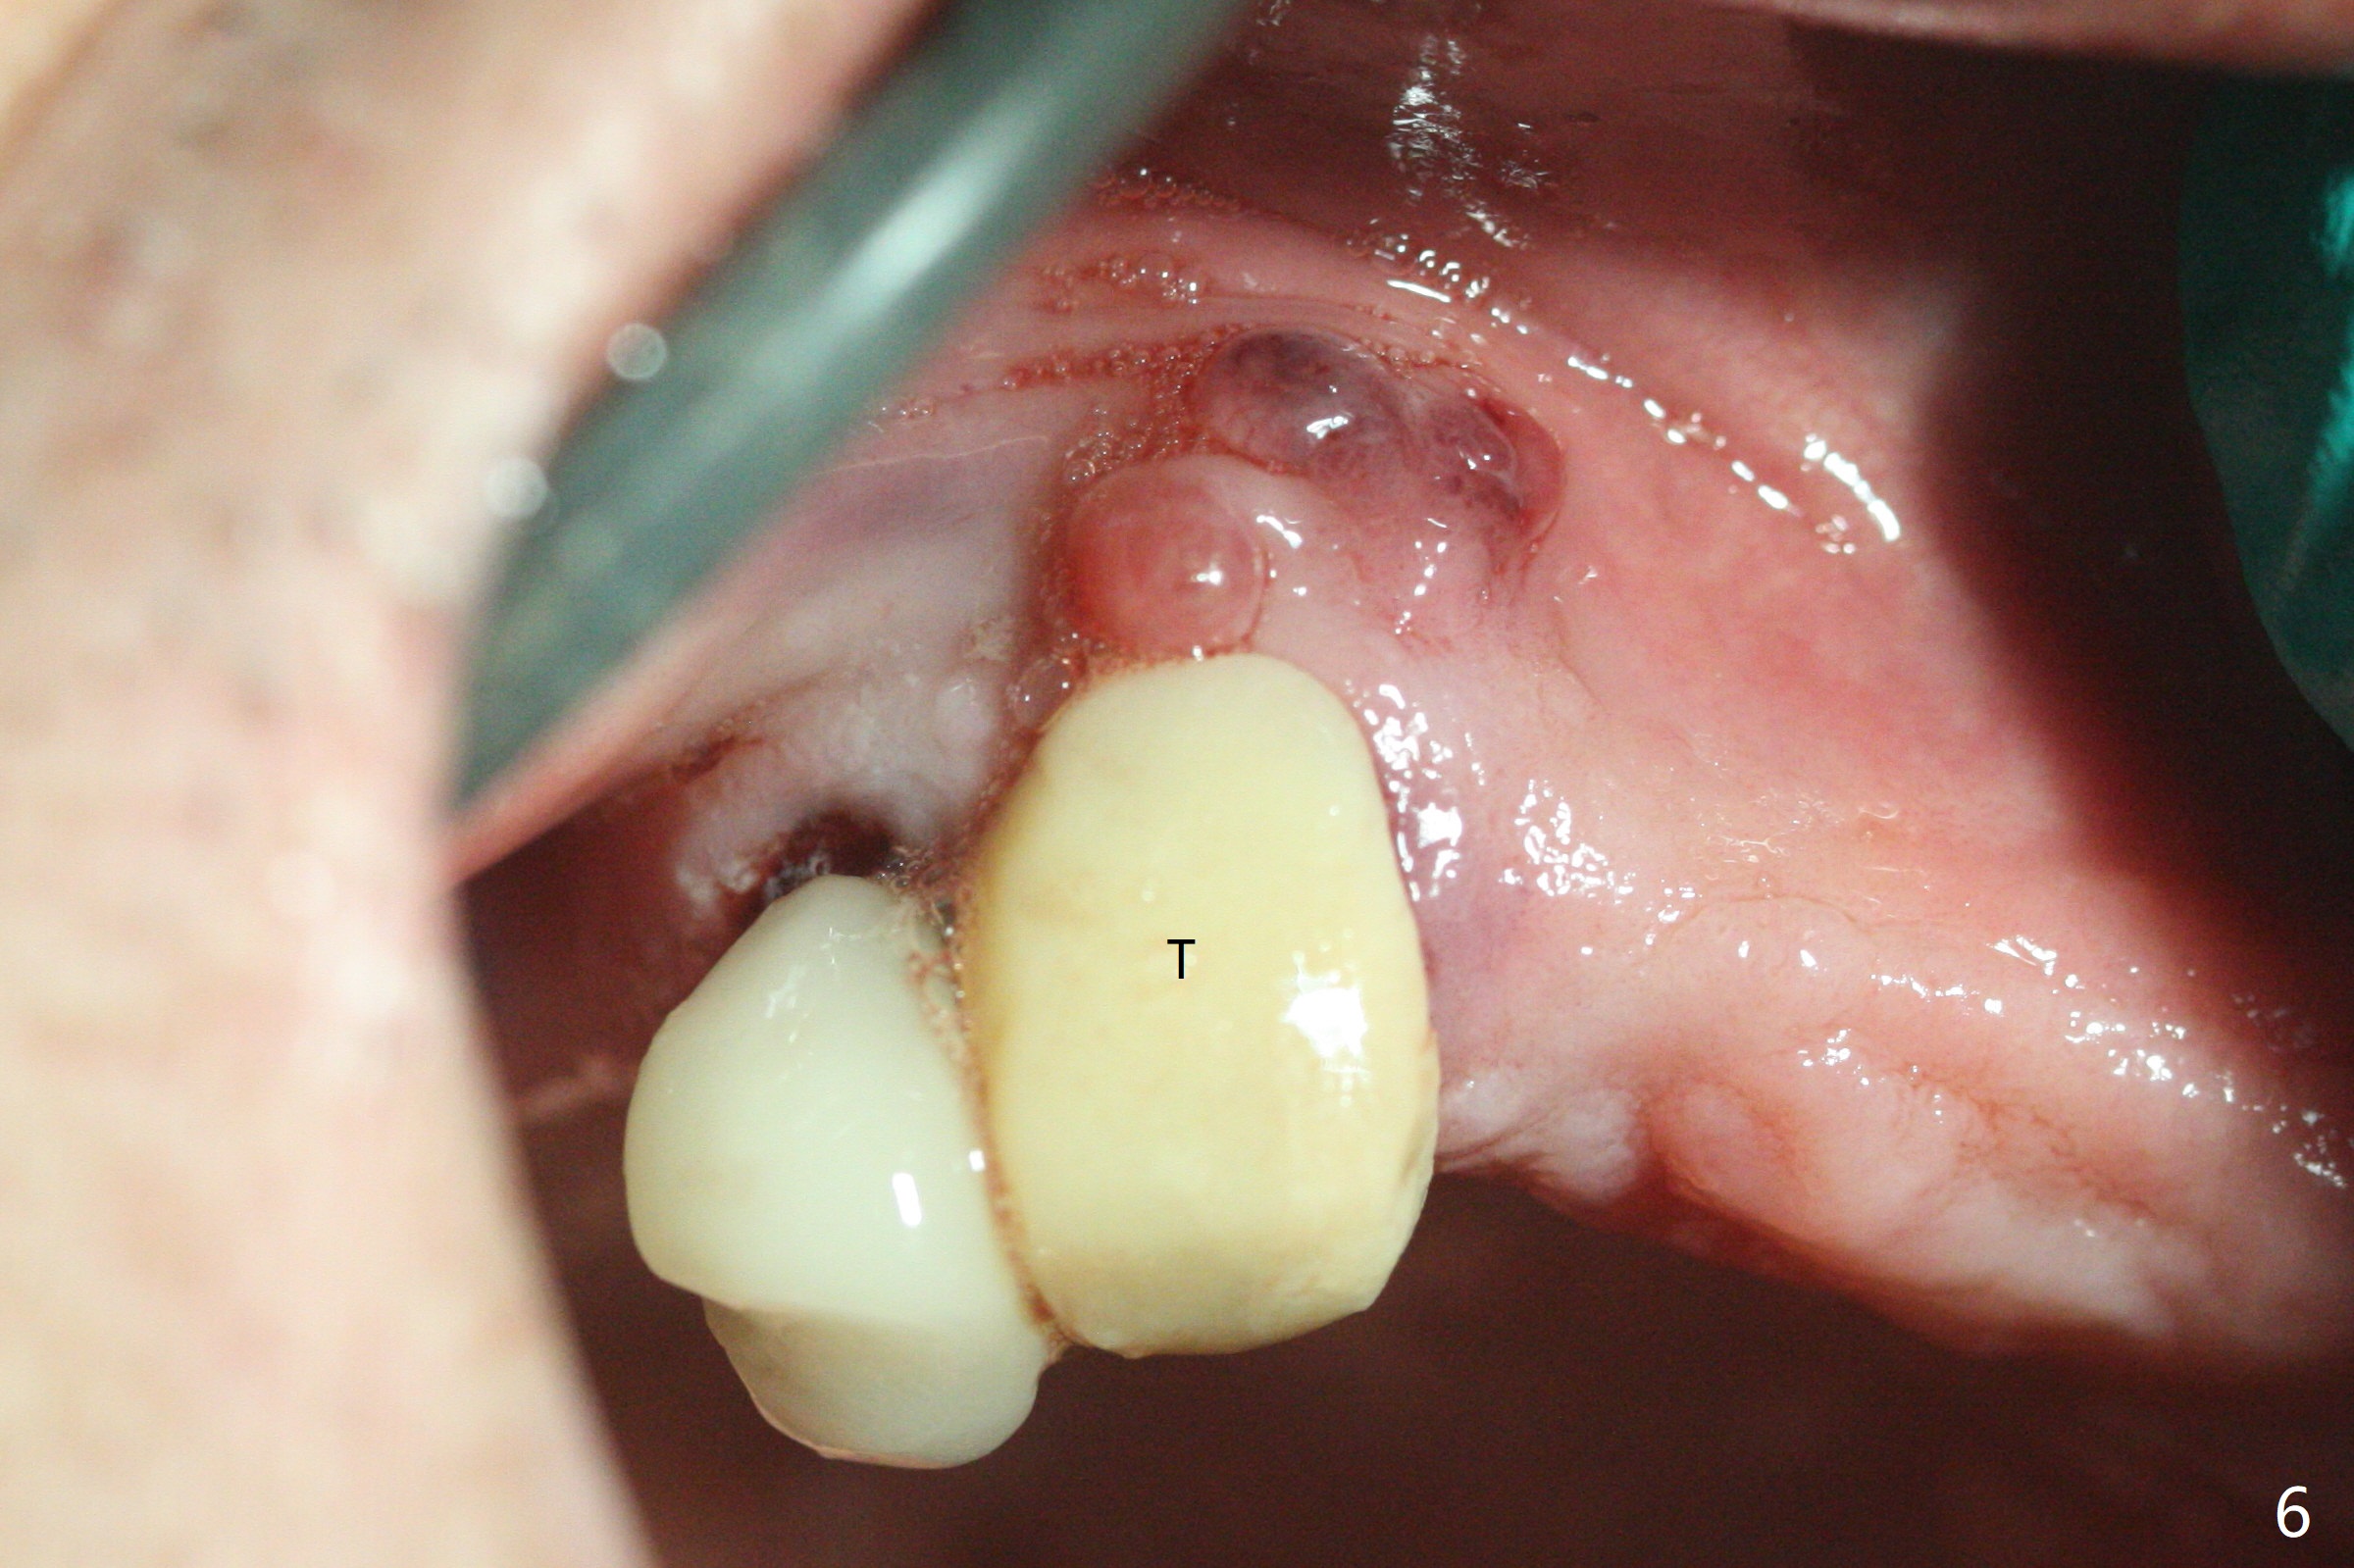

部分断裂的5号牙颊侧根尖有3个瘘道(图一),五类(颈部)缺损,严重牙龈退缩。牙齿拔除过程中断裂,需要手机切断拔除,颊侧骨板缺失,钻洞起源于牙槽窝腭侧(融合根,图二,五),植入4x13毫米长植体,根尖骨大约4毫米,植体也卡入近中,远中骨壁,扭力大于35Ncm,即刻放置基台,颊侧间隙(图三至五:*)放入粘性骨粉,牙槽窝口用PRF穿过基台关闭(图五),接着制作临时牙冠(图六:T),多次衬里严密关闭牙槽窝,而咬合面低,最后插入活动托牙(图七:RPD,左侧有两个基牙)。Return to Protect Graft Torque Xin Wei, DDS, PhD, MS 1st edition 05/18/2021, last revision 05/18/2021